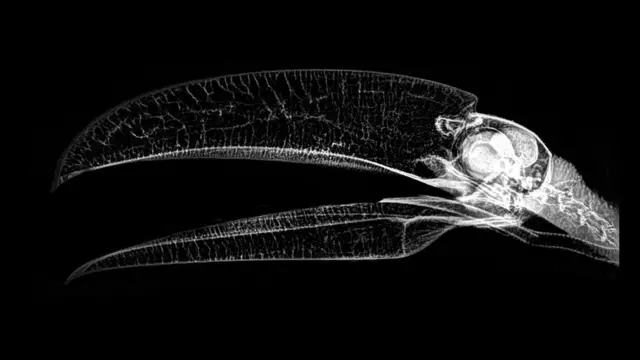

జంతువులను ఎక్స్రే తీస్తే ఎలా కనిపిస్తాయి?

అమెరికాలోని ఓరేగాన్ రాష్ట్రంలో ఉన్న జూ ఒకటి జంతువుల ఎక్స్రే చిత్రాలను పోస్ట్ చేసింది.

జంతువుల ఆరోగ్యాన్ని పరిశీలించేందుకు ఈ జూలో పరీక్షలు నిర్వహిస్తుంటారు. ఆ పరీక్షల సందర్భంగా తీసినవే ఈ చిత్రాలు.

జంతువుల ఆరోగ్యాన్ని పరిశీలించేందుకు ఈ ఎక్స్రే చిత్రాలు చాలా బాగా ఉపయోగపడుతుంటాయని జూ తెలిపింది.